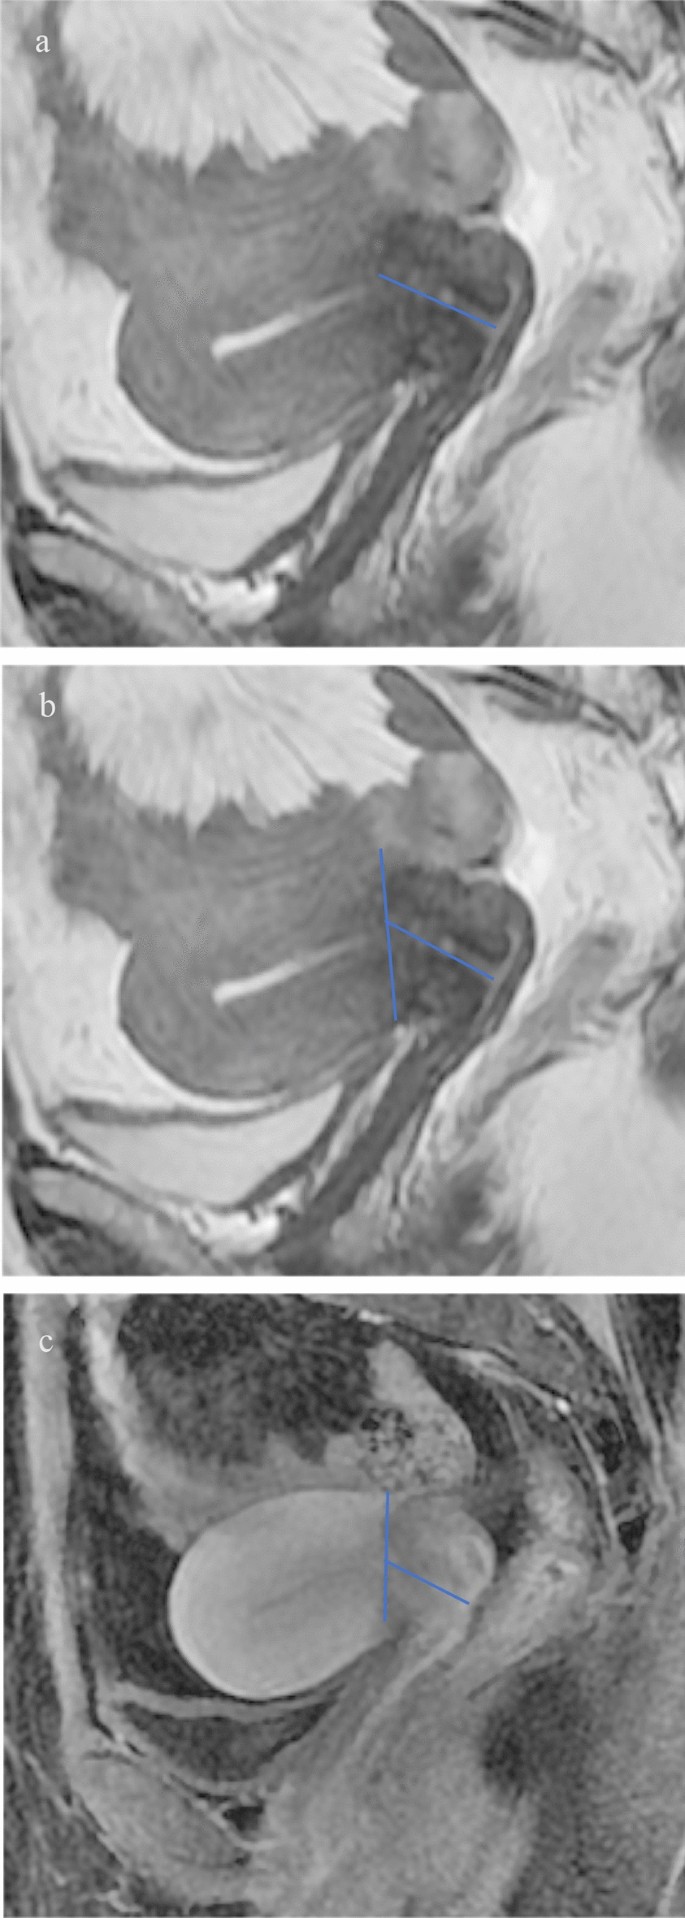

The logistic regression analysis showed that A history of cesarean section (p < 0.001), irregular vaginal bleeding for more than three months (p < 0.001), cervical adenomyosis (p = 0.043) was not conducive to locating the internal os of the cervix by MRI, while the menopausea was a a contributing factor (p = 0.001). A history of cesarean section is unfavorable for the measurement of cervical stroma and the formation of the physiological curvature of the uterus and cervix on T2WI images (Fig. 2). Abnormal uterine bleeding over three months and premenopause are unfavorable for forming the cross-section between the uterine body and cervix on dynamic enhanced T1WI images. Adenomyosis of the cervix is not favorable for observing the cross-section of the physiological curvature of the uterus and cervix on T2WI images (Fig. 2). Detailed results are shown in Table 3.

The sagittal T2WI image, the uterus is in an anteverted position, with the thickened endometrium protruding into the cervical canal. The patient had a history of cesarean section surgery and a scar formed in the muscle layer of the lower part of the anterior uterine wall. This is accompanied by deep endometriosis and adenomyosis of the posterior cervical wall, affecting the formation of the physiological curvature of the uterus, and the distinction between the lower part of the uterine body and the cervical stroma is unclear (a). The sagittal dynamic enhanced scan image, the enhancement degree of the uterine body and the cervix is different, the uterine body is stronger than the cervix, and the cross-section formed by the difference in enhancement degree can be used to locate the internal os of the cervix (b).

Sagittal T2WI, measure the cervical length from the start of the low signal of the cervical stroma (a). Sagittal T2WI, measures the cervix length starting from the cross-section where the physiological curvature of the uterus is formed (b). Sagittal dynamic enhancement scanning image, measure the cervix length beginning from the uterine and cervical enhancement junction (c).